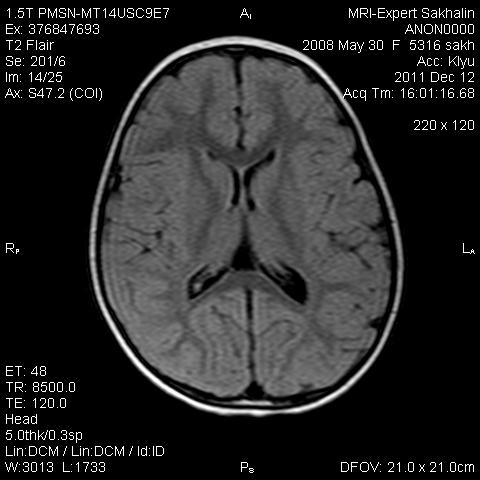

Девочка 3 года.В анамнезе -родовая травма-внутрижелудочковые кровоизлияния 1-2 ст.Задержка психического развития.Со слов мамы, "бывают истерики, хватается ручками за голову, особенно затылочную часть".Как интерпретировать изменения в желудочках, в задних рогах?Ликворную кисту ЗЧЯ отметила.

В желудочках могут быть маленькие кисты сосудистого сплетения, но это ничего особенного - вариант нормы. Кисту в ЗЧЯ, кстати, тоже не заметил, где она?

Киста не совсем киста, но нижняя ретроцеребеллярная цистерна незначительно расширена- я указала.

А вот гипоинтенсивное по Т2 в заднем роге левого бокового желудочка?В других последовательностях нет.

справа киста сосудистого сплетния -она же ксанутрогранулема,пртекаетбессимптомно.в эру доКТ и МРТ диагнстировались только на аутопсии,влевомсплетении -фокус пониженного МРС -возможно обезыствление или гемосидерин  ( ведь было кровоизлияние?)

Спасибо, Ирина!Было кровоизлияние, причем с обеих сторон.

Здравствуйте! Извините что вклиниваюсь в вашу дискуссию. В дополнение ко всему сказанному мне показалось что для трехлетнего ребенка желудочки несколько великоваты, больше слева. Ликворные пространства не симметричны, опять больше слева. В складочках мозга мелкие, пока, кисточки. Может быть попробовать исключить церебральный арахноидит? Пункцию делали?

Коллеги, в рамках ликбеза: а такое (некоторое) расширение субарахноидального пространства (не вполне характерное для 3-летнго ребенка), расценивается как гидроцефалия (заместительная, открытая, последствие ишемически-гипоксического синдрома) или нет?